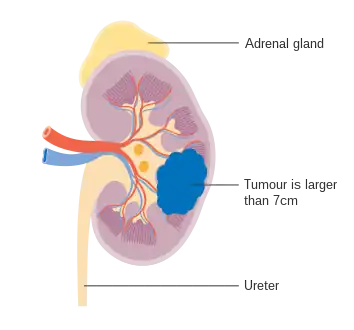

Staging is the process that helps determine the extent and spread of the disease.[45] Renal cell carcinoma is the only type of kidney cancer that can be staged. The first step of staging follows the TNM staging system proposed by the Union International Contre le Cancer that is widely used among cancers in other organs.[15] The TNM staging system classifies the primary tumor (T), lymph nodes (N) and distant metastasis (M) of the disease. The American Joint Committee on Cancer (AJCC) published a Cancer Staging Manual revision in 2010 that describes the values of TMN for renal cell carcinoma.[46][15]

The primary tumor of renal cell carcinoma is categorized in the table below, as according to the AJCC 8th Edition Cancer Staging Manual:[47][48]

| II | T2, N0, M0 | Tumor >7 cm; limited to kidney |

| T2a, N0, M0 | Tumor 7-≤10 cm; limited to kidney | |

| T2b, N0, M0 | Tumor >10 cm; limited to kidney | |

Stage 2 kidney cancer Stage 3 kidney cancer

Stage 3 kidney cancer Stage 4 kidney cancer